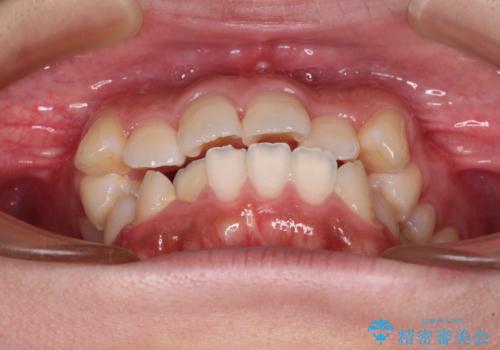

くちばしのような前歯が気になる ワイヤー装置による抜歯矯正治療

- 前歯の出っ歯と口元の閉じにくさを気にして来院された患者様です。

口元を積極的に引っ込めるために、上下左右の小臼歯4本を抜歯することとしました。